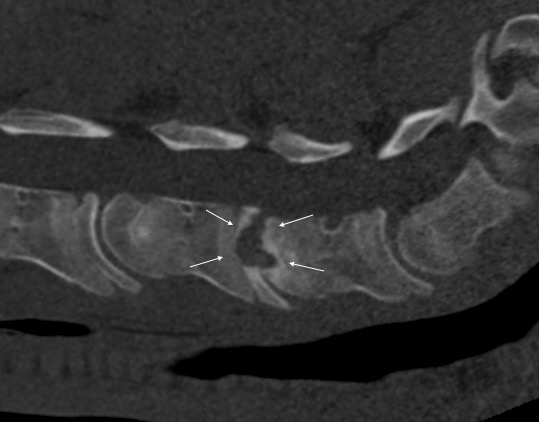

Pokud neurologické vyšetření potvrdí ataxii (stupeň 1–5), je potřeba stanovit její přesnou příčinu. Nejčastěji se jedná o zúžení páteřního kanálu v oblasti krčních obratlů, kde pak dochází k útlaku míchy – Wobblerovu syndromu. Existují ale i další příčiny ataxie, které je potřeba vzít na vědomí, například vrozené abnormality krčních obratlů (vertebrální malformace), úrazy krční páteře, nádory, virové infekce (EHV), bakteriální infekce (abscesy, záněty meziobratlových plotének a kostí) (obr. 2a, b, c), parazitární infekce nebo některé toxiny.

Obrázek 2a, b: Hříbě s ataxií a horečkou způsobenou zánětem kostí obratlů C6–C7. Na CT je jasně patrné výrazné poškození kostí v důsledku infekce (bílé šipky). Na obrázku 2b je stejný případ z jiného pohledu